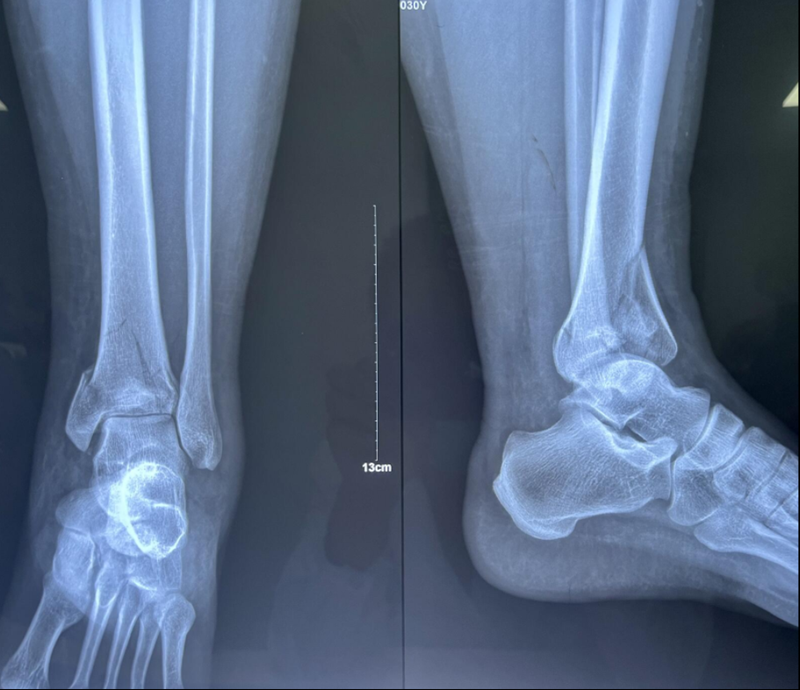

x男,30岁,体重100kg,在五楼擦玻璃时坠落到四楼致伤2天。

诊断:左胫骨平台后柱骨折,后交叉韧带撕脱骨折,左踝关节pilon骨折3型。

图8 Pilon骨折3型